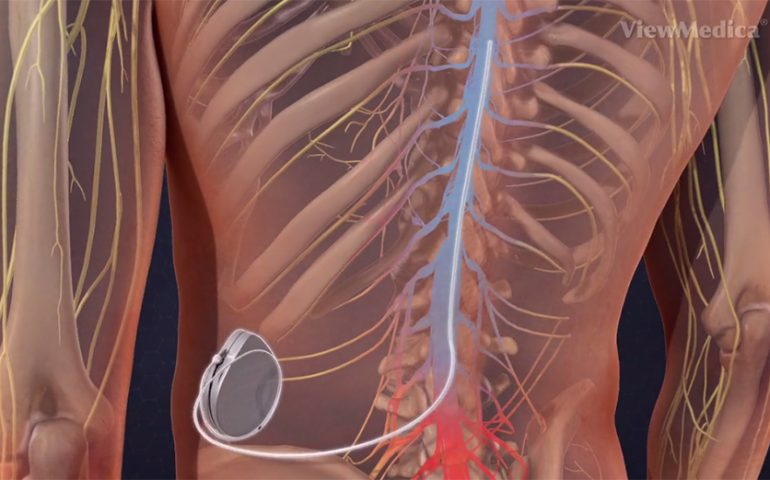

Treatments for spasticity range from therapy to muscle relaxant medications, such as Baclofen. Baclofen is prescribed orally for patients with spasticity, but to get desirable effects in some people, higher doses must be used sometimes. However, higher doses of baclofen taken orally usually have side effects such as feeling sleepy, tired, dizzy or weak, feeling nauseous, headaches, blurred vision, and problems sleeping (3). For those who require higher doses to treat their spasticity, an alternative delivery method is available, which is to use a surgically implanted pump to continuously supply the spinal cord with Baclofen, allowing for the use of higher doses without side effects. Known as an intrathecal baclofen pump, this device is a round implant about the size of a hockey puck used to store about 6 months’ worth of medication, and it delivers it to the spinal cord intrathecally–in the cerebrospinal fluid that fills the space between the spinal cord and the tissue that surrounds it–via a catheter. Baclofen relaxes the constant contraction of the muscles, so this method of treatment helps restore fluidity in the individual’s movements and eases the tone in their muscles. However, not everyone can go through with this surgery (such as myself). Actually, I had a surgical injection of Baclofen a few weeks ago (09/26/2023) to test if it would work for me before going through with the implantation of the device. Results: it helped somewhat, but the side effects of the surgery itself (lumbar puncture) were severe enough that I’d rather not go through that again. I’ve gone 10 years without it, and all the while graduated from high school with honors and UCSD with a bachelor’s degree in Cognitive Science, I think I can function perfectly okay without it.